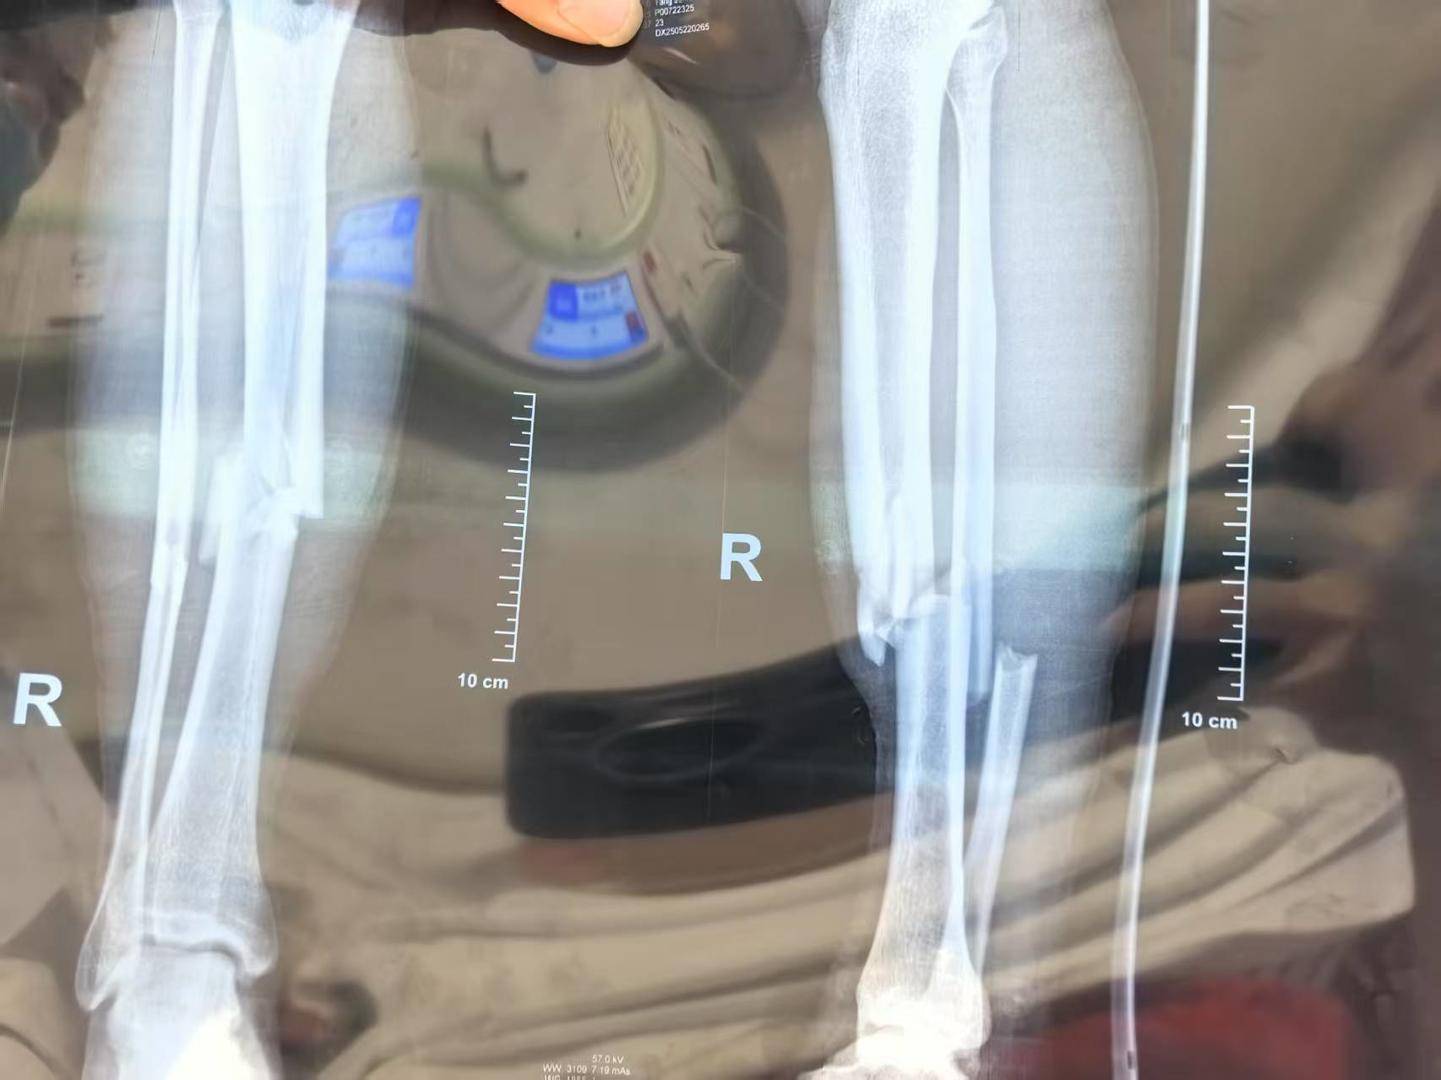

受伤后,小杨被场边的救护车送往医院,比赛恢复后继续进行。最终,榕江队以2:1战胜对手,获得这项赛事的总冠军。而在医院的小杨,被确定为胫腓骨骨折。

▲小杨医学影像显示为胫腓骨骨折 受访者供图